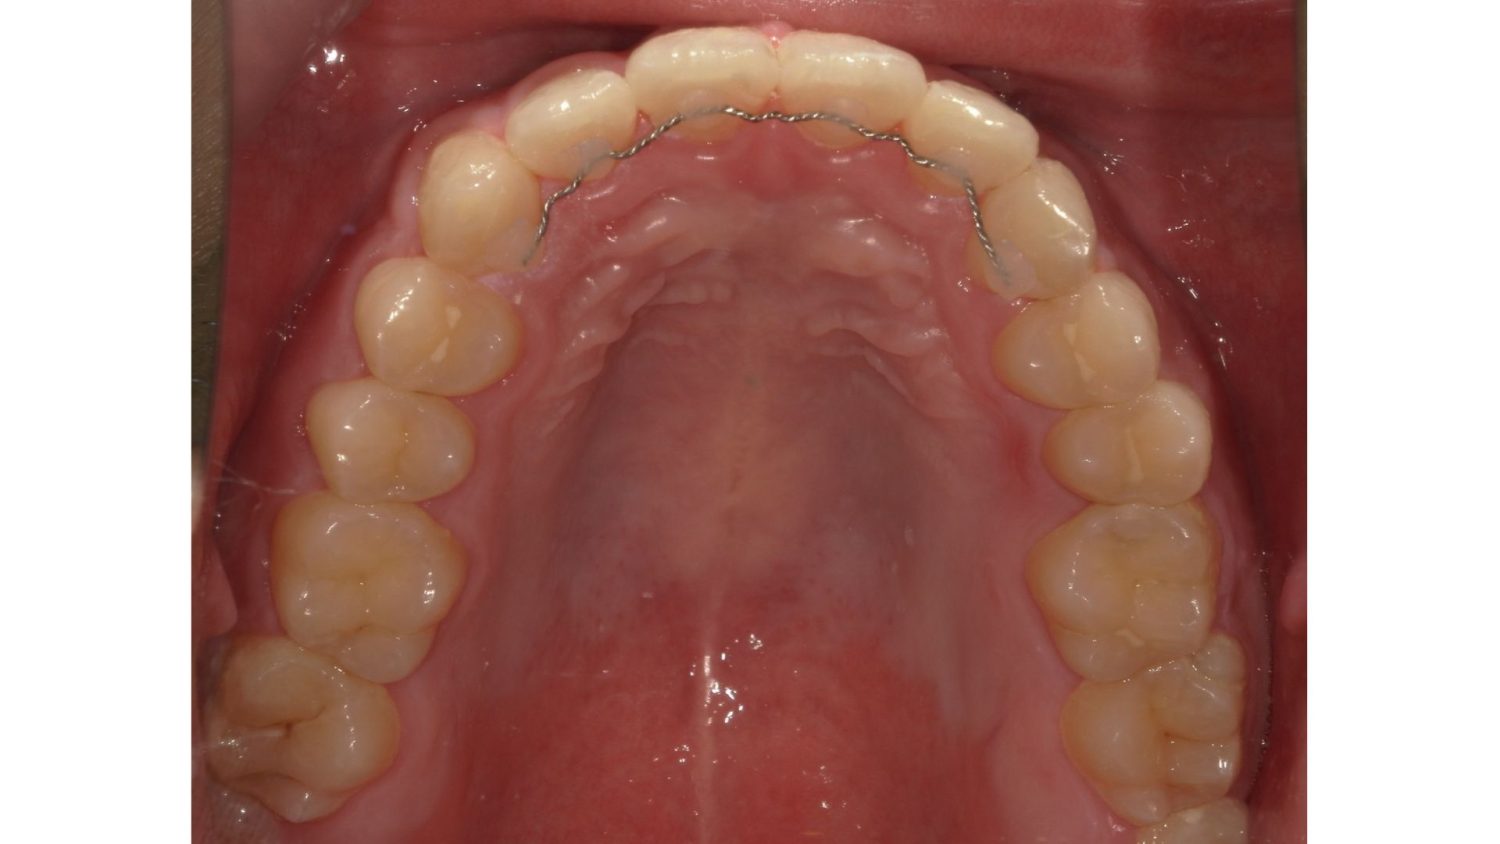

After

前歯だけの矯正の症例紹介②

前歯だけの矯正の症例紹介③